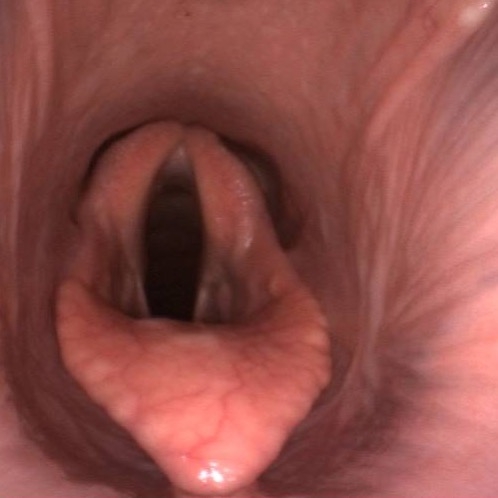

Bronchoskopie: Untersuchung der Atemwege

Mit einer Bronchoskopie beim Pferd lassen sich die Atemwege vom Nasengang bis in die Bronchien untersuchen. Typische Einsatzgebiete sind:

- Verdacht auf Equines Asthma

- Abklärung von Atemwegserkrankungen

- Untersuchung von Kehlkopf, Luftsäcken und Luftröhre

- Entnahme von Sekret- oder Gewebeproben für eine gezielte Therapie

Während der Untersuchung wird das Endoskop schonend über die Nüster eingeführt. Auf dem Bildschirm sind Schleimablagerungen, Entzündungen oder andere Veränderungen direkt sichtbar.